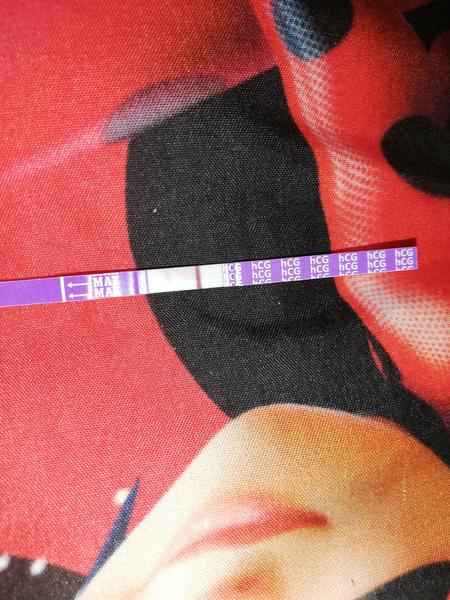

Práve som si urobila test. Je pozitívny?

Ahoj žienky test prave urobeny co si onom myslíte

Mas slabe kramy plus druhy test tak tan nic neni.Podla mna nie si tehotna. A neviem podla mna ked zena menstruuje vtedy sa testy nerobia podla mna.Skus takych 5 dni po menstruacii test.Skusate o babo?

Viem ze nic nevidite ani ja na foto nevidím poriadne ale na živo vidno niečo 🤦♀️

@sandra151 tvoja kamarátka si robila len jeden test? Ci viac mne tu baby píšu ze ten test Ktory vyšiel Pozitívny (do polí ciarka) ze je premoceny ale ako vidis na foto hore robila som si vten den ešte jeden a je tam niečo slabe aj ked ťažko vidno

Možno si bola a odišlo to takže na teste ti ukázalo zostatk hcg skús znova o 2 dní ak nebude nič je to jasné ak bude silnejší tak je to tam .ináč ja to vidím

Ak mas piaty den ms tal skor nie si tehu...okrem toho ciarka.nie je uplna.takze chybny test...pisu to aj v pribalovom letaku...